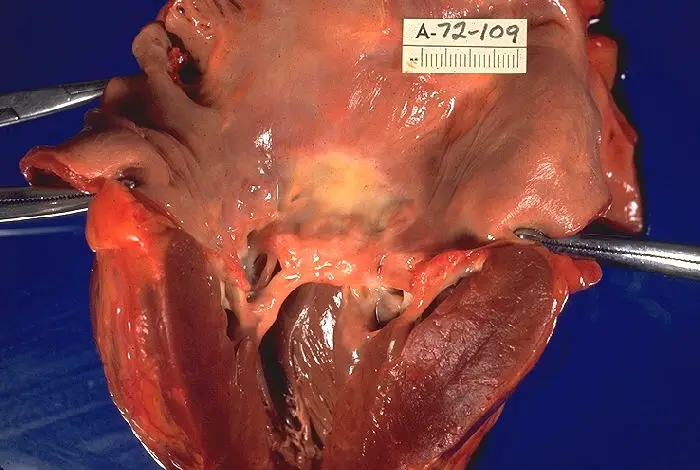

The mitral valve is the most affected cardiac valve.

Small vegetations accrue on the valve along the lines of closure that result in mitral regurgitation.

Chronic rheumatic heart disease develops when rheumatic fever-related valve scarring leads to stenosis with the classic fish-mouth appearance.

In chronic rheumatic heart disease, the chordae tendineae and cusps thicken as a result of the mitral valve being involved almost always.

Quite often the aortic valve is involved, which results in the commissures fusing together.